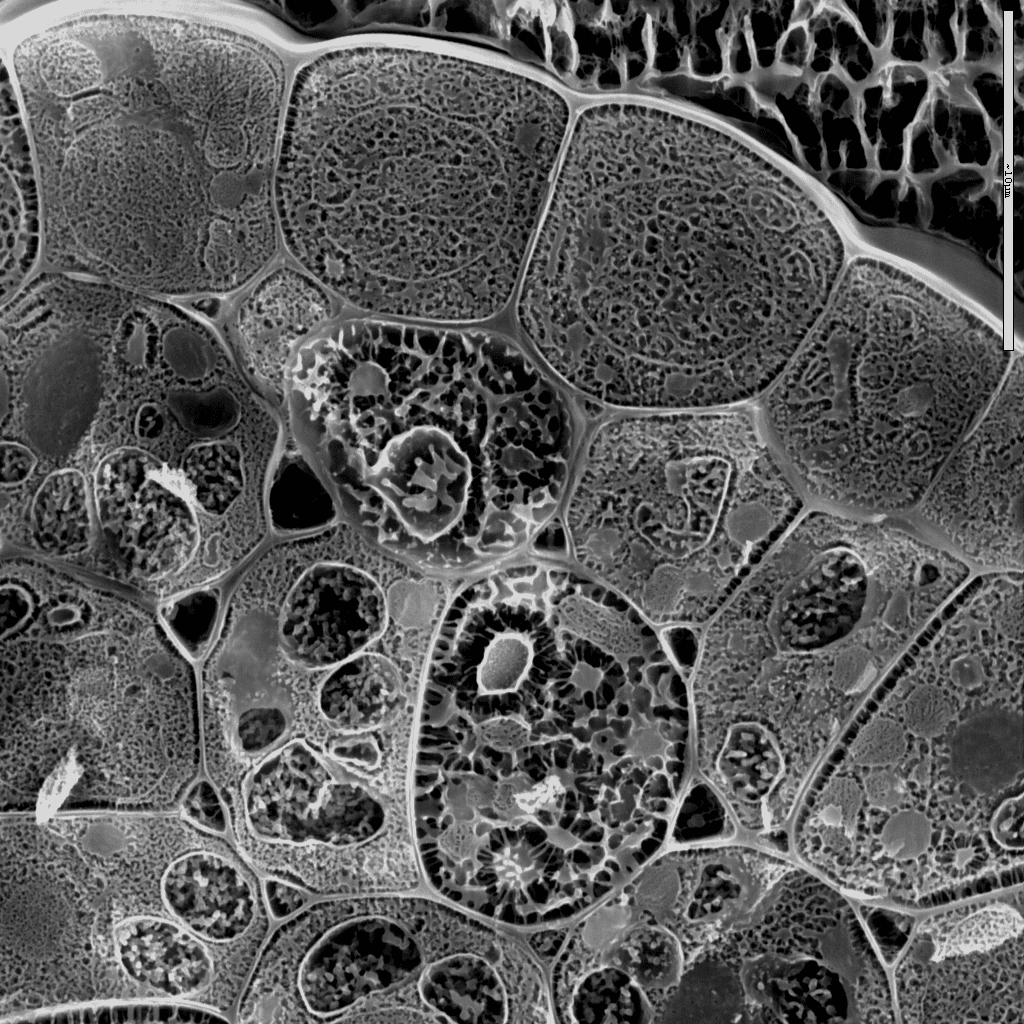

Images of cells courtesy of Prof Antonio D Molina García and Dr Aline Schneider Teixeira